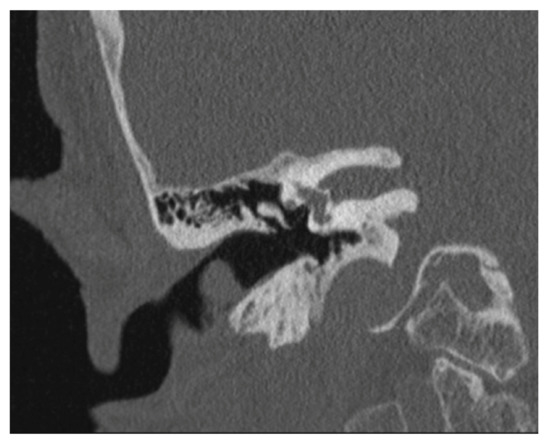

| Our case | 1/87/f | posterior | A | 13 × 10 × 6 mm | End-Exc | No rec |